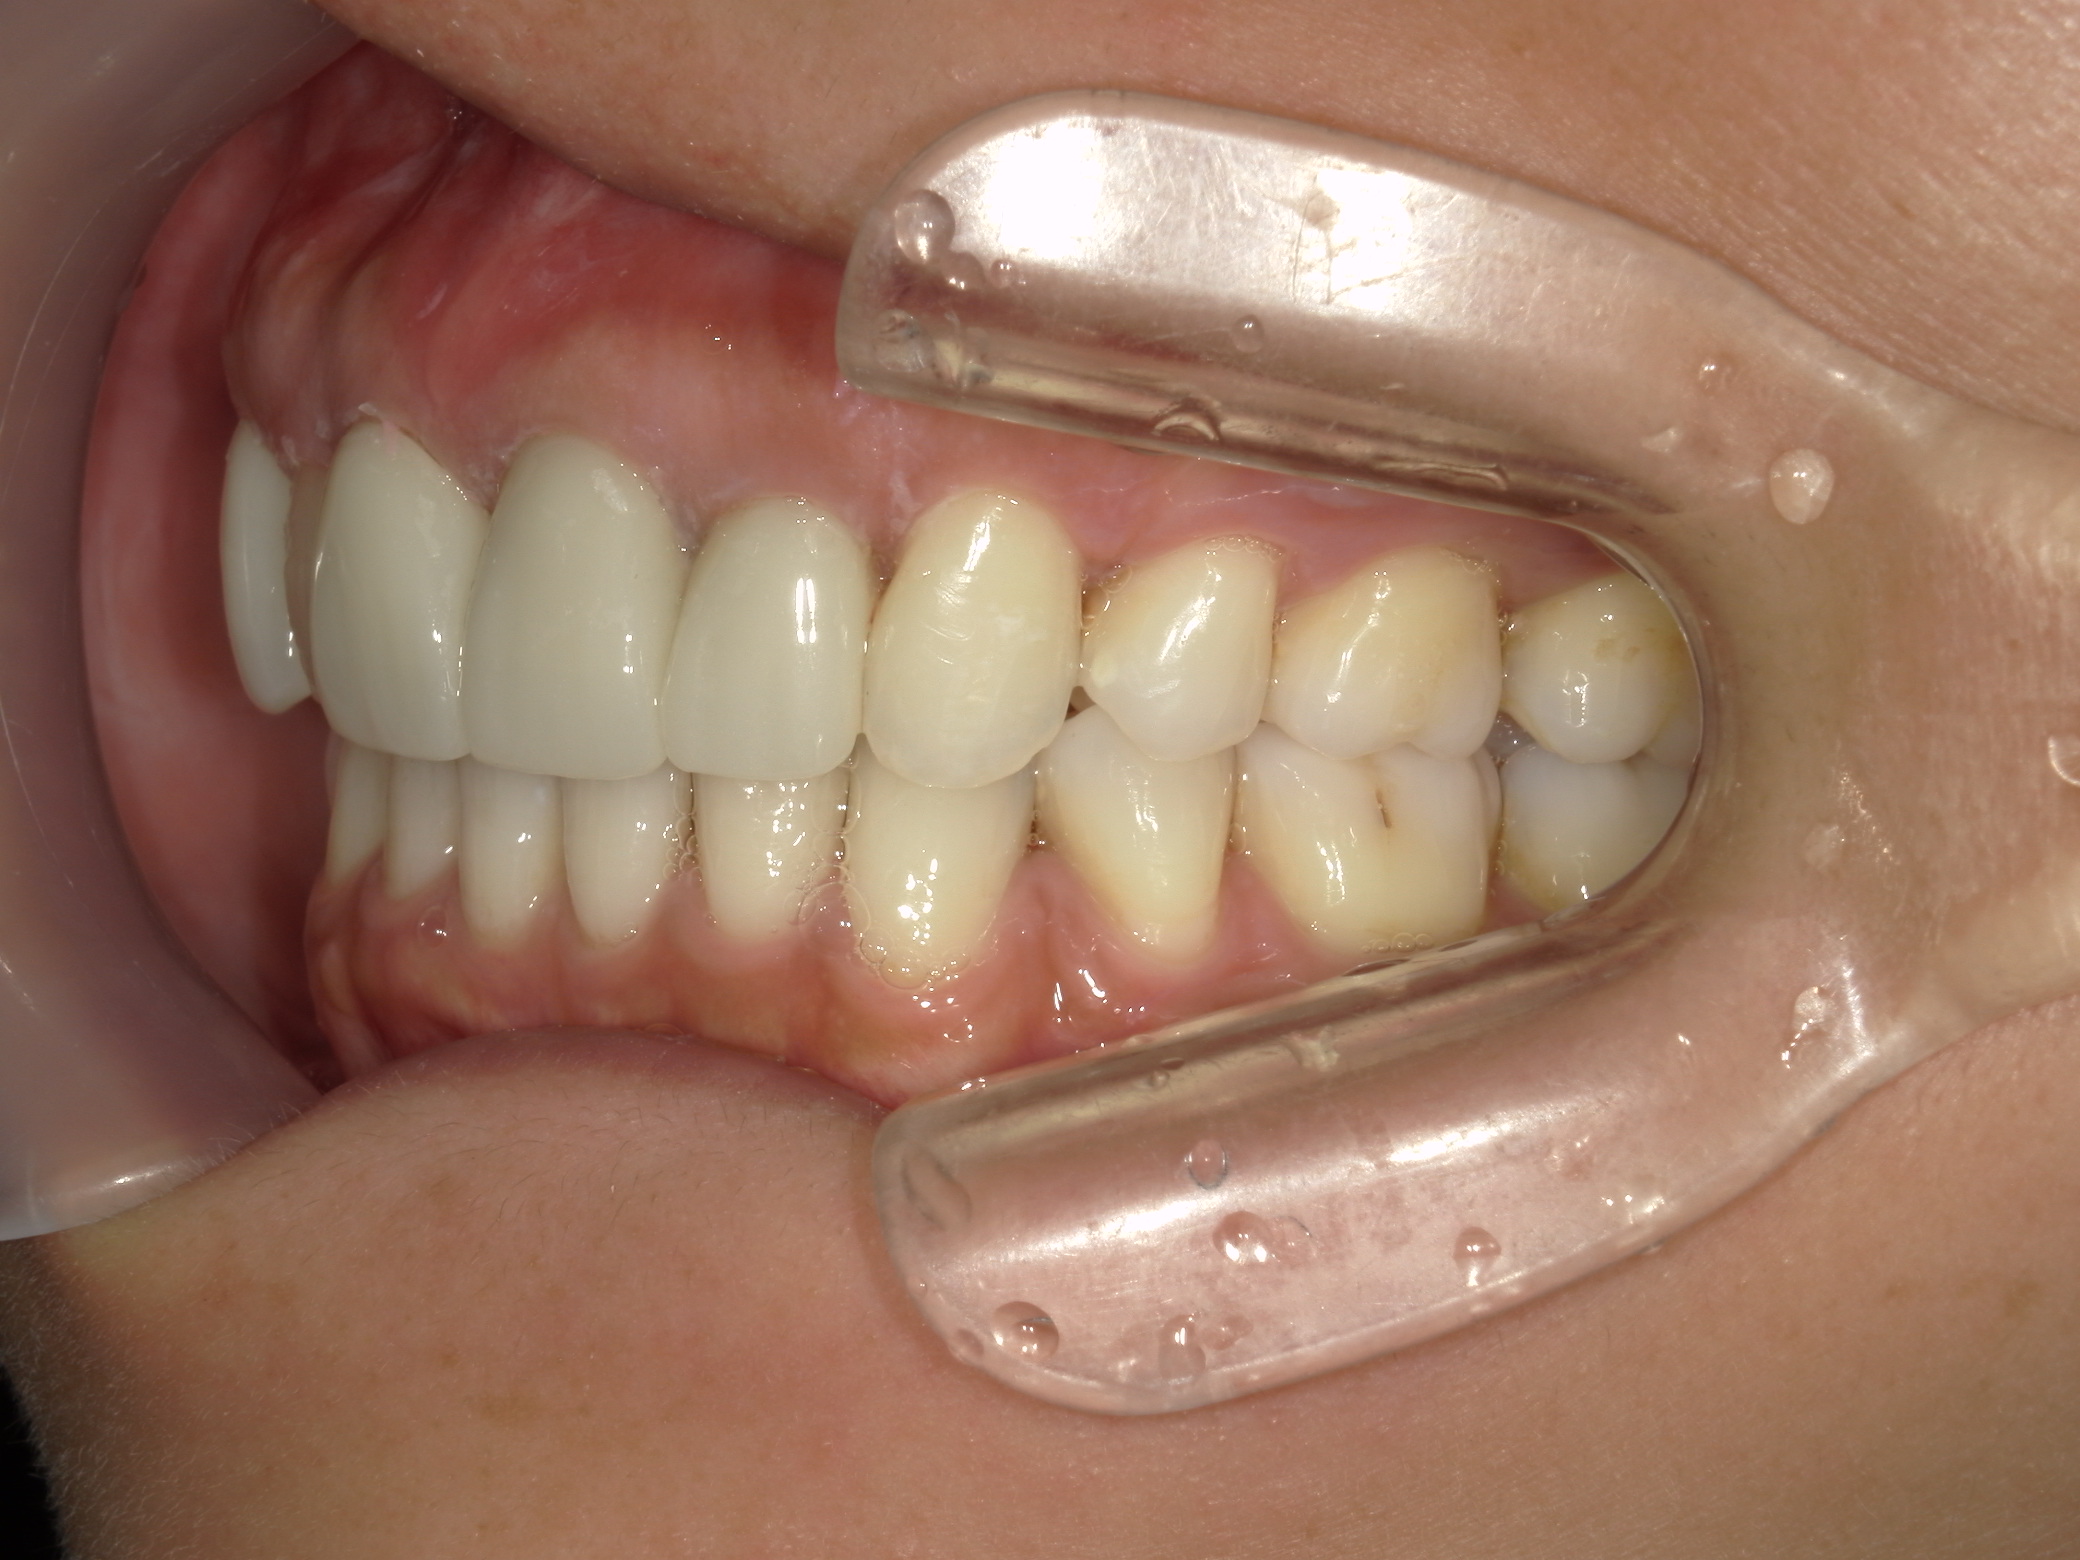

全顎ワイヤー矯正 症例(82)

主訴: 前歯の歯並びが気になる。

上下左右 第一小臼歯(4本)、左右上 親不知(2本)を抜歯。

ミニインプラント、アップライトスプリングを併用。

矯正前に左右上前歯4本を仮歯に変え、矯正治療後にセラミック(SHT)に冠せなおしました。

カテゴリー : ガタガタ(叢生)